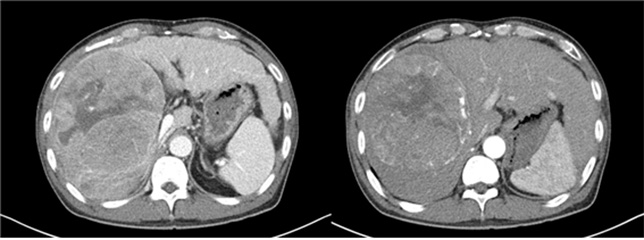

- 병리조직학적으로 정의되는 질환으로 임상적으로 대상성 간경변증과 비대상성 간경변증으로 분류되며 비대상성 간경변증은 복수, 정맥류 출혈, 간성뇌증, 황달이 있는 경우로 정의할 수 있습니다.

- 진단은 주로 임상적으로 이루어 지며, 문진, 신체검사, 영상검사와 피검사등이 필요합니다.

- 원인으로는 만성 B, C형 간염, 알코올성 간염, 비알코올성 지방간, 원발성 담즙성 간경병증등이 있으며, 흔하지 않은 유전적, 대사성 간질환도 있습니다.

- 합병증은 식도, 위 정맥류 출혈, 간경변성 복수, 간성뇌증, 간신증후군, 간암의 발생이 있습니다.